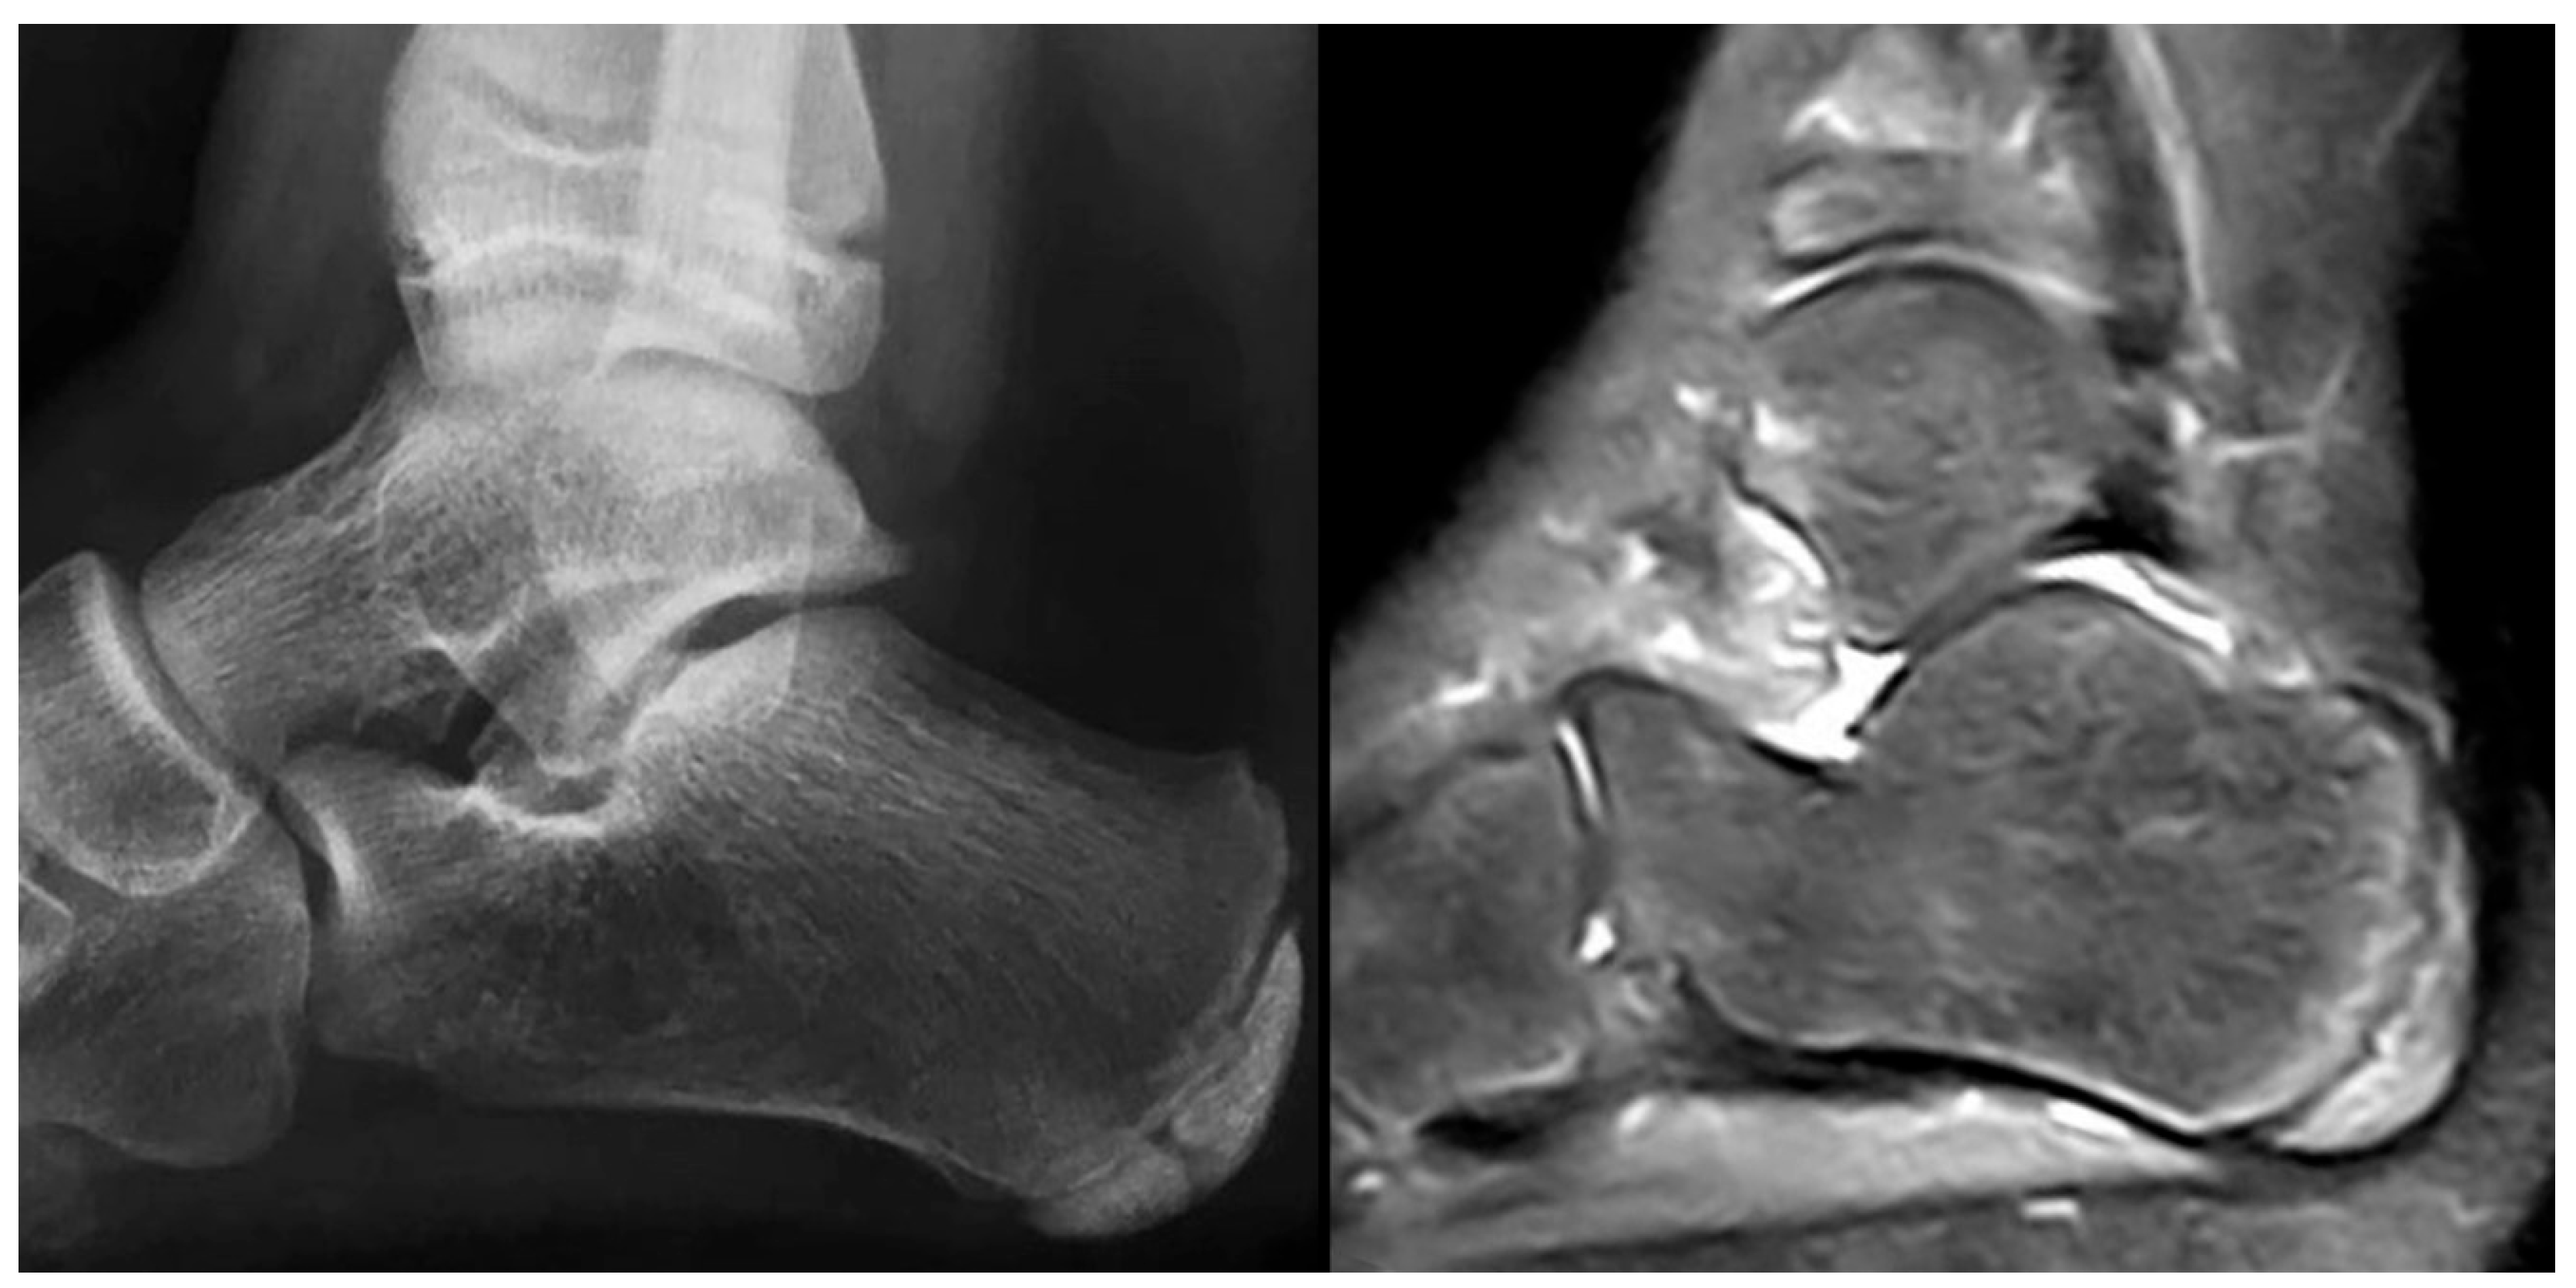

Plain radiographs are the cornerstone of imaging in the diagnosis of lesser metatarsal osteochondrosis. In the early stages of the disease, when supported by a suggestive clinical presentation, obtaining a comparative radiograph of the contralateral foot can be a useful diagnostic tool (Figure 9).

Figure 9.

Radiograph of a symptomatic 10-year-old female patient showing early sclerosis and flattening of the second metatarsal head on the left foot, compared to the contralateral side.

In the later stages, radiographs may reveal characteristic changes including subchondral sclerosis, fragmentation, and flattening of the affected metatarsal head (Figure 10 and Figure 11). In some cases, the presence of joint space narrowing or bony irregularities may also be observed. However, early changes, such as bone marrow edema or subtle cartilage damage, may not be visible on standard radiographs. MRI is particularly useful in the early stages of the disease, as it can detect bone marrow edema, which is a sign of active bone inflammation and necrosis, even before structural changes become apparent on radiographs (Figure 10, Figure 11 and Figure 12).

Figure 10.

Radiograph (left) and MRI (right) of a 17-year-old female patient showing necrotic changes and initial flattening of the second metatarsal head.

Figure 11.

Radiograph (left) and MRI (right) of a 15-year-old male patient with osteochondrosis of the third metatarsal head and early signs of deformation.